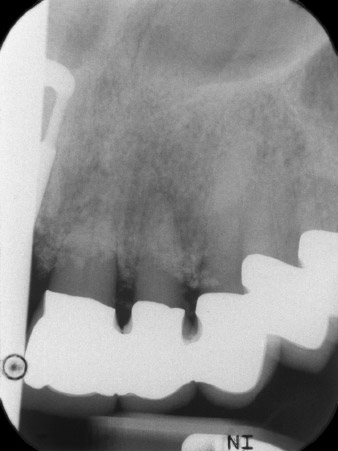

initial radiological findings

Fig. 1: The initial radiological findings revealed a splinted crown restoration requiring replacement. When the restoration was removed, teeth 21 and 22 were unintentionally extracted along with it.

The x-ray revealed horizontal bone loss around teeth 21 and 22 (Fig. 1). When the crown block was removed, these teeth were unintentionally extracted with it.